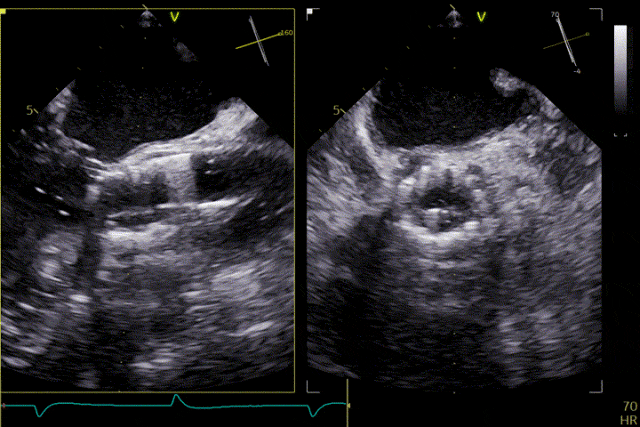

術前超聲